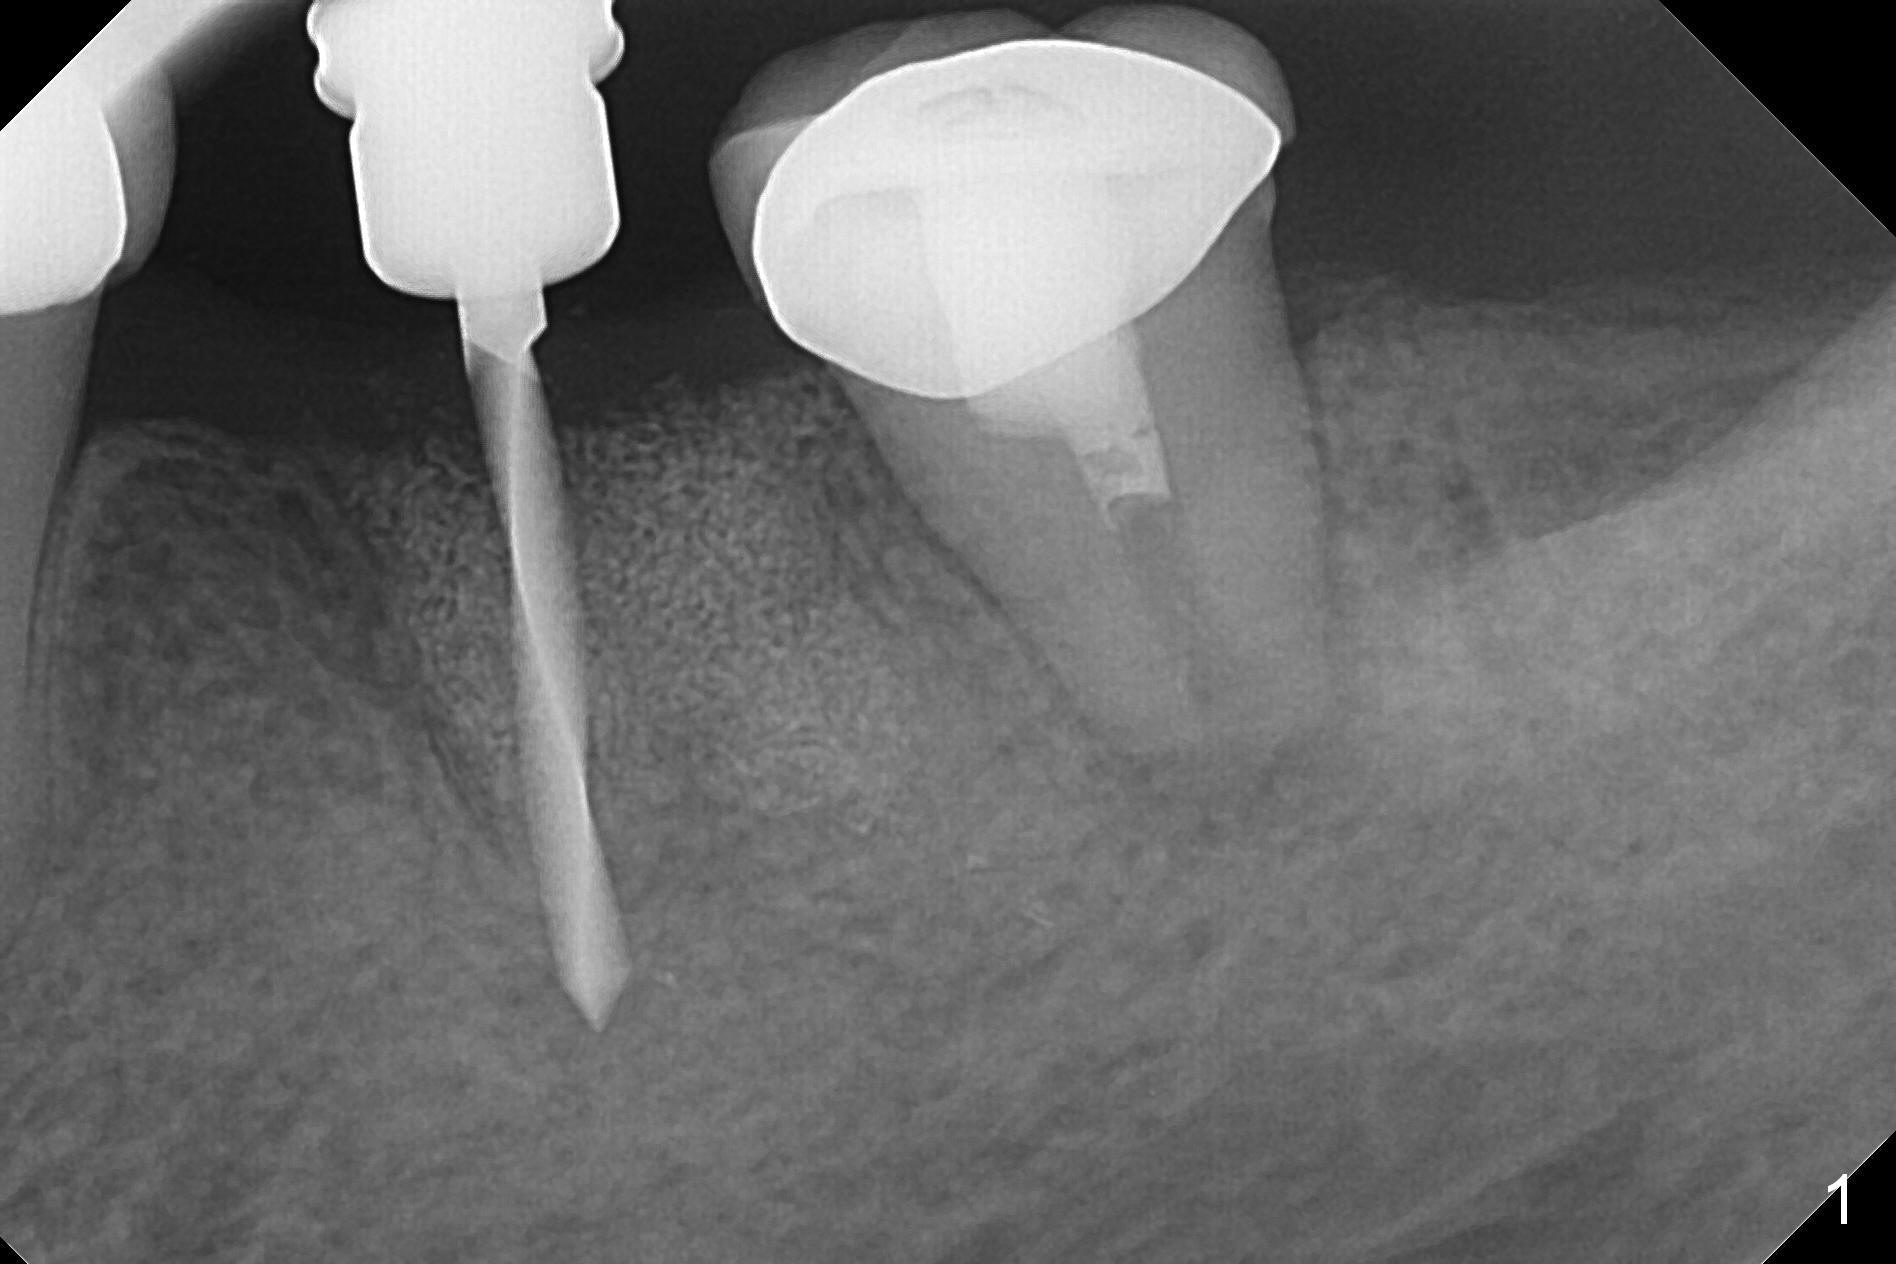

After making a 10 mm incision at the site of #19, #15c blade is used as an osteotome to start bone expansion, followed by Magic Split and Magic Expander (ME, 3 mm in diameter).  The depth is approximately the bottom of the mesial socket.  The osteotomy beyond the socket has to be done with 1.6 mm pilot drill (Fig.1) in combination of ME.  Following ME 4.3 mm and Magic Drill (MD) 3.8 mm for 15 mm (gingival level), a 4.5x11 mm dummy implant is placed with 50 Ncm (Fig.3); the implant looks narrow for the edentulous space.  After ME 4.8, MD 4.3 for 13 mm and Final Drill for 15 mm, a 5x11 mm IBS is inserted with >50 Ncm (Fig.3).  With 2 more turns of the implant, a 6.5x4(2) mm abutment is placed (Fig.4).  Periodontal dressing is applied around the abutment for additional retention.  A provisional is fabricated 3 weeks postop.  The provisional and abutment are loose 4 months postop (Fig.5).  After retightening the abutment, impression is taken for final restoration.  There is no bone loss 1 year 3 months post cementation (Fig.6).  After use of #100 file (Fig.7), the canal is debrided with #140 file with 1.5 mm shorter in working length with placement of Calcium Hydroxide paste.  Pain gets worse post RCT retreatment. There is limited native bone for primary stability when an immediate implant is placed (red dashed line: the superior border of the Inferior Alveolar Canal).  Prepare IS regular and extra wide kits and tissue-level implants (>5 mm).  Socket preservation may be done instead.  If the socket is large and the vein is not so small, prepare PRF.  In fact blood drawing fails.  When the tooth is extracted, it is sensitive to remove granulation tissue.  Socket preservation is done with Vanilla graft at #18 (Fig.8); there is ~3.5 mm bone between the bottom of the single socket and the Inferior Alveolar Canal (red dashed line).  The socket at #18 seems to have healed 4 months post extraction (Fig.19), but the bone height appears to have been reduced (compare Fig.10,11).  The buccolingual width is also decreased (Fig.12,13).  A 4.5 or 5.0x10 mm implant is appropriate for the site (Fig.14).  There is no bone loss at #19 (which may be associated with the bone expansion) 1.5 years post cementation (Fig.15).  Therefore the osteotomy at #18 will be assisted with bone expanders after 2.2 mm drill.